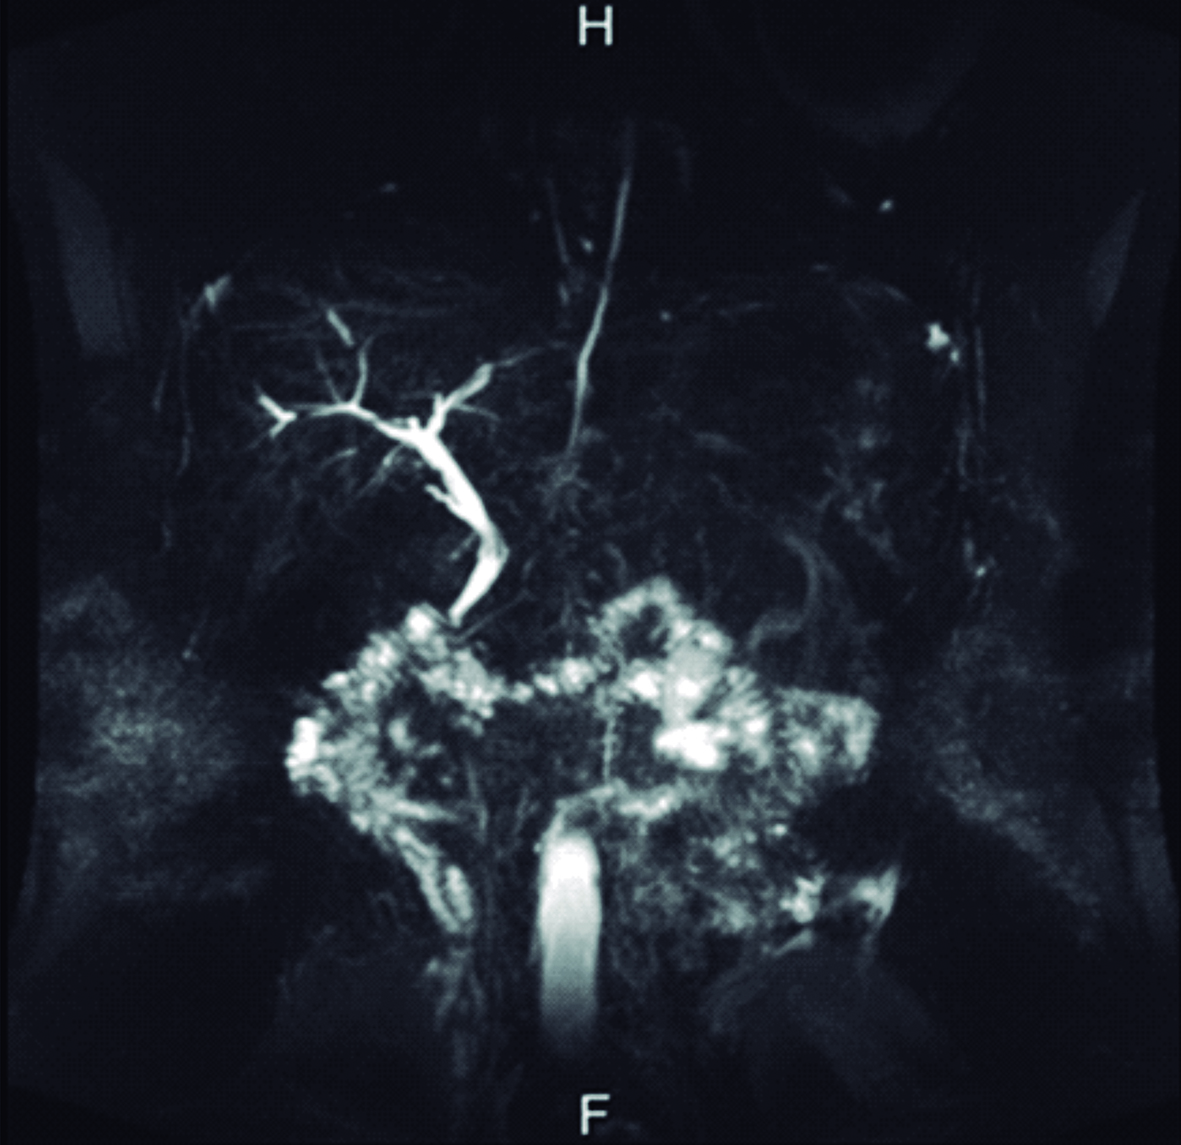

El ultrasonido de abdomen realizado al ingreso mostró vía biliar principal dilatada, a predominio del conducto hepático izquierdo en cuyo interior se observó imagen trilaminar, alargada, sin sombra acústica posterior, compatible con parásito. El extremo cefálico del parásito alcanza el origen de los canalículos de los segmentos póstero-laterales izquierdo y su extremo caudal se extiende dentro de la luz del conducto hepático común y el colédoco. El diámetro mayor del colédoco alcanzó 12mm, el parásito se detectó alcanzando la zona de la papila duodenal, estando plegado sobre sí mismo dentro de la vía biliar principal (Fig. 1).

Figura 1. Ultrasonido en modo B

a) Corte transversal a nivel de epigastrio, en el cual se identifica colédoco dilatado (flecha azul), ocupado por el Ascaris plegado sobre sí mismo (flecha amarilla).

b) Corte longitudinal sobre el colédoco supraduodenal, en el cual se observa el

Ascaris plegado sobre sí mismo (flechas amarillas) dentro del colédoco dilatado

(flecha azul). H: Lóbulo hepático izquierdo, E: Corte transversal del antro gástrico,

VP: Vena porta.

En el ultrasonido, la apariencia de los helmintos depende de la sonda empleada. Con transductores convexos de baja frecuencia se visualizan típicamente en un corte longitudinal como una imagen trilaminar y sin sombra acústica, las líneas ecogénicas externas corresponden a las paredes del parásito y la imagen lineal ecogénica en su interior corresponde al tracto digestivo del mismo. Si se visualizan transversalmente en un conducto biliar dilatado, aparecen como una imagen tubular, en diana con bordes ecogénicos y centro anecogénico. Con una sonda lineal de alta frecuencia (mayor a 7.5MHz) los helmintos se observan en corte longitudinal como una imagen de 4 líneas, representando las dos exteriores la interfaz entre el parásito y lo que lo rodea y las dos interiores el intestino de la lombriz. (5, 7, 13) Estas imágenes características fueron las que llevaron al diagnóstico en la paciente que se presenta en este caso. Algunas veces puede observarse la movilidad de los helmintos vivos, pueden estar enrollados y si son múltiples, pueden llenar completamente el conducto biliar y producir el “signo de espagueti”. Si están muy compactados en los conductos biliares, pueden aparecer amorfos y manifestarse como pseudotumores hiperecogénicos. (6) Debe realizarse exploración de la vía biliar principal y accesoria ya que en ocasiones se ubican dentro de la vesícula biliar. También debe valorarse el conducto pancreático para descartar Ascaris en esta localización. El empleo de la sonda lineal en ocasiones es de utilidad para mejorar la resolución espacial y de ese modo caracterizar mejor los parásitos. (1)